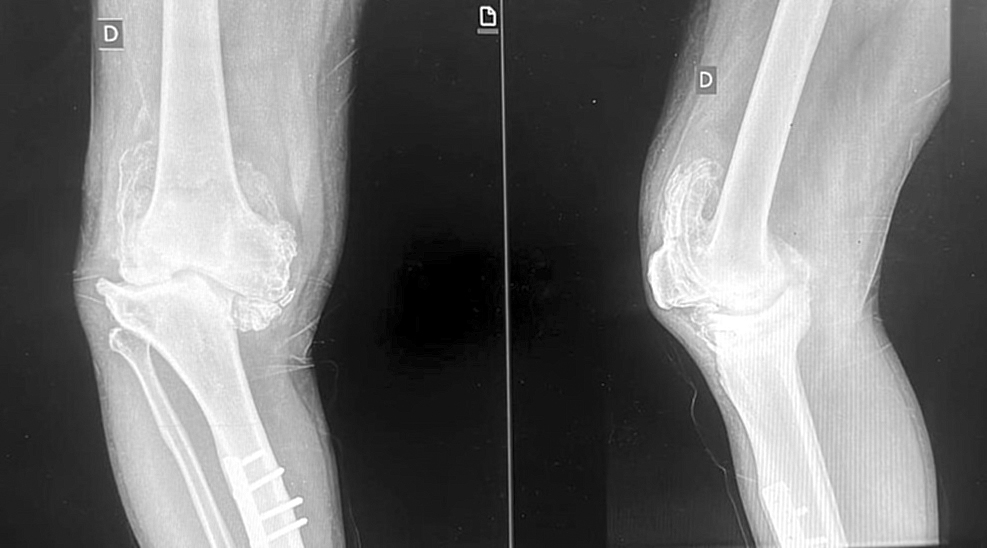

El Dr. César Salinas, médico del plantel de Traumatología del Hospital Central recordó que: “En esa oportunidad le habíamos realizado una cirugía de reemplazo articular de la rodilla izquierda con una prótesis total de rodilla de tipo primaria. Hace 8 años le habíamos intervenido y actualmente volvió a acudir, pero por un dolor en la rodilla derecha”.

“Entonces vimos la posibilidad de llevar a cabo la cirugía de la rodilla derecha al constatar la gran deformidad y artrosis que presentaba el paciente. El plan consistió en realizar un remplazo articular y corregir la deformidad con una prótesis total de tipo bisagra”.

“Con la colaboración del Departamento de Servicios Quirúrgicos de IPS Central pudimos realizar la cirugía de forma exitosa. El paciente presentaba un un varo y artrosis severa (grado IV) en la rodilla derecha. Una enfermedad degenerativa de la rodilla que con una prótesis primaria no se podría corregir la deformidad. Sin embargo, los especialistas de cirugía de rodilla de IPS ya realizan este tipo de cirugías de prótesis para grandes deformidades” señaló el médico.